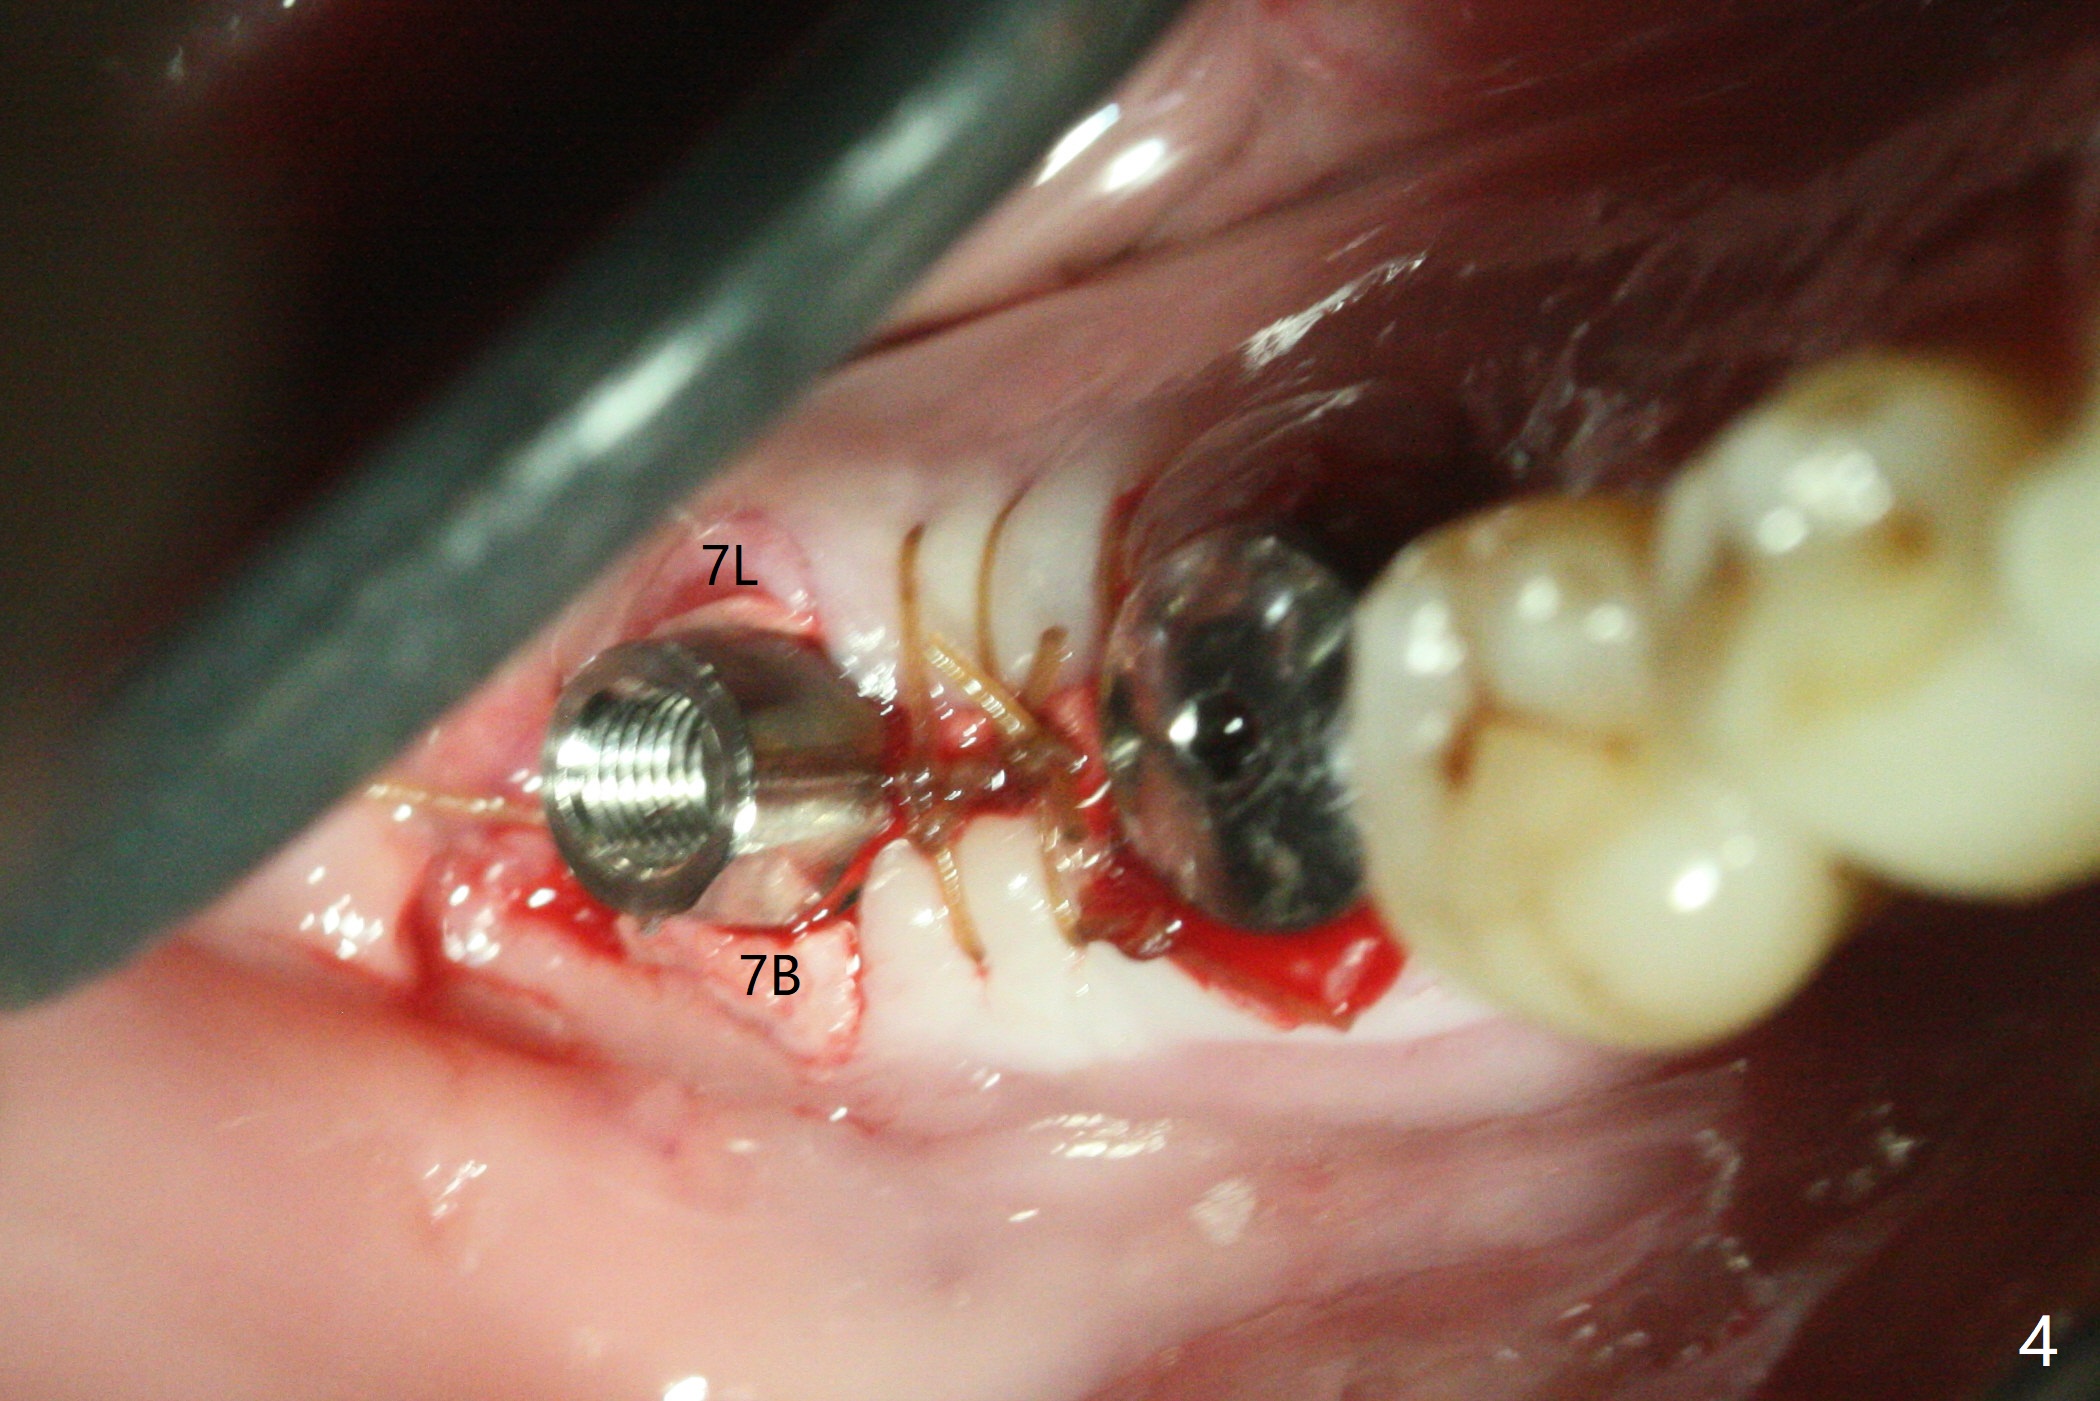

54岁男,右下6,7位点保留后7个月回来植牙,植牙床是个平面(图一),今后两个牙齿之间龈乳头一定缺乏,如何重建?放置导板,稍微使用环形钻头,在6,7植牙床上形成标记(图二),然后切开,植入植体,6扭力低,7高,所以安置愈合(6x5毫米)和修复(5.5x4(4)毫米)基台。原来导板设计把植体植入牙槽嵴(图三:白虚线)下1-2毫米,自动提高植体间牙槽嵴,接着把钻洞产生的骨粉放在后者上缘(*),由近中和远中基台固定。最后覆盖胶原膜,缝合(图四)。原来导板需要切除的角化龈保留住了(图四:7B,7L)。放入修复基台目的是利用它的高度固定牙周敷料。术后3个月7牙槽窝愈合(位点保存后10个月,图五:*),植体间牙槽嵴仍旧高(箭头),6放置修复基台,准备做临时牙冠。右上7反合,需要做局部矫正(图六)。病人非常感激术后三个月制作的临时牙冠(连体)。术后五个月对临时牙冠进行修改:6牙合面垫高(图七:*),这样上下7牙合面分开,上7颊侧放置矫正器,下7牙圈(舌侧有cleat),两者之间安置橡皮筋,上7就可以自由往舌侧移动。术后8.5个月全景片和CT显示植体种植牙槽嵴下(图八至十),这也是重建龈乳头基础。